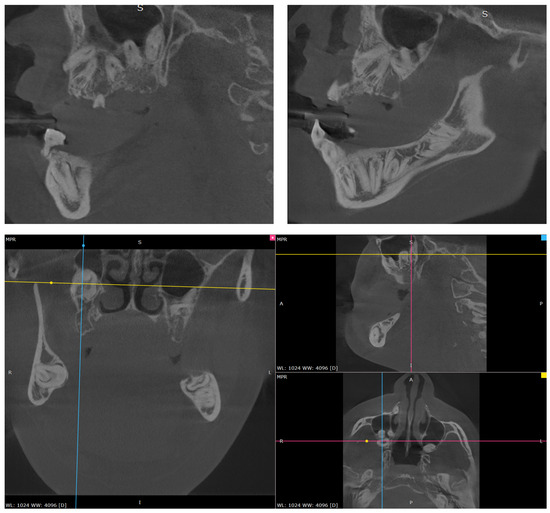

Extraoral examination revealed facial asymmetry, a dolichofacial growth pattern, and a concave facial profile (Figure 1a,b). As for the patient’s dental situation, intraoral clinical evaluation showed the presence of teeth 3.1, 5.3, and 7.4, along with a root remnant likely corresponding to 2.5 (Figure 2a,b,c,d,e). She showed a skeletal class III relationship due to the absence of erupted teeth. The patient’s mandible appeared prognathic, while the maxilla was severely hypoplastic [19,20]. The orthopantomography (OPG) revealed the presence of multiple impacted teeth, most of which exhibited abnormal morphology and incomplete development (Figure 3) [21]. The OPG was acquired using standard panoramic settings (66–70 kVp, 8–10 mA, exposure time 12–14 s) to obtain a comprehensive overview of dental development, impactions, and bone morphology. CBCT imaging was performed using a small-to-medium field of view (FOV 8 × 8 cm), 90 kVp, 5 mA, and a voxel size of 0.2 mm, allowing detailed assessment of tooth morphology, root development, and three-dimensional spatial relationships essential for treatment planning. Cone-beam computed tomography (CBCT) confirmed the findings and aided in treatment planning (Figure 4) [22]. Clinical photographs and radiographic records were collected, and the patient was enrolled in a multidisciplinary dental and prosthetic rehabilitation program.

Figure 4. Multiplanar CBCT reconstructions confirm the three-dimensional precise location and morphological abnormalities of the multiple impacted dental elements.

3.2. Radiographic Findings

Orthopantomography (OPG) and Cone-Beam Computed Tomography (CBCT) confirmed significant dental anomalies. The majority of the permanent dentition was impacted, including all permanent elements from 1.1 to 1.8, 2.1 to 2.4 and 2.8 (maxilla), 3.2 to 3.8, and 4.2 to 4.8 (mandible). Most of these impacted teeth exhibited abnormal morphology and incomplete development. Element 4.1 was absent due to prior extraction for advanced tooth decay at age 11. Such a severe pattern of dental impaction and tooth loss resulted in the observed near-complete edentulism, a finding that severely impaired oral function.